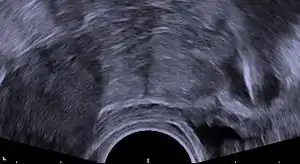

Immediately prior to insertion, the clinician will perform a pelvic exam to determine the position of the uterus.[20] After the pelvic exam, the vagina is held open with a speculum.[36] A tenaculum is used to steady the cervix and uterus.[36] Uterine sounding may be used to measure the length and direction of the cervical canal and uterus in order to decrease the risk of uterine perforation.[37] The IUD is placed using a narrow tube, which is inserted through the cervix into the uterus. Short monofilament plastic/nylon strings hang down from the uterus into the vagina. The clinician will trim the threads so that they only protrude 3 to 4 cm out of the cervix and remain in the upper vagina. The strings allow the patient or clinician to periodically check to ensure the IUD is still in place and to enable easy removal of the device.[20]